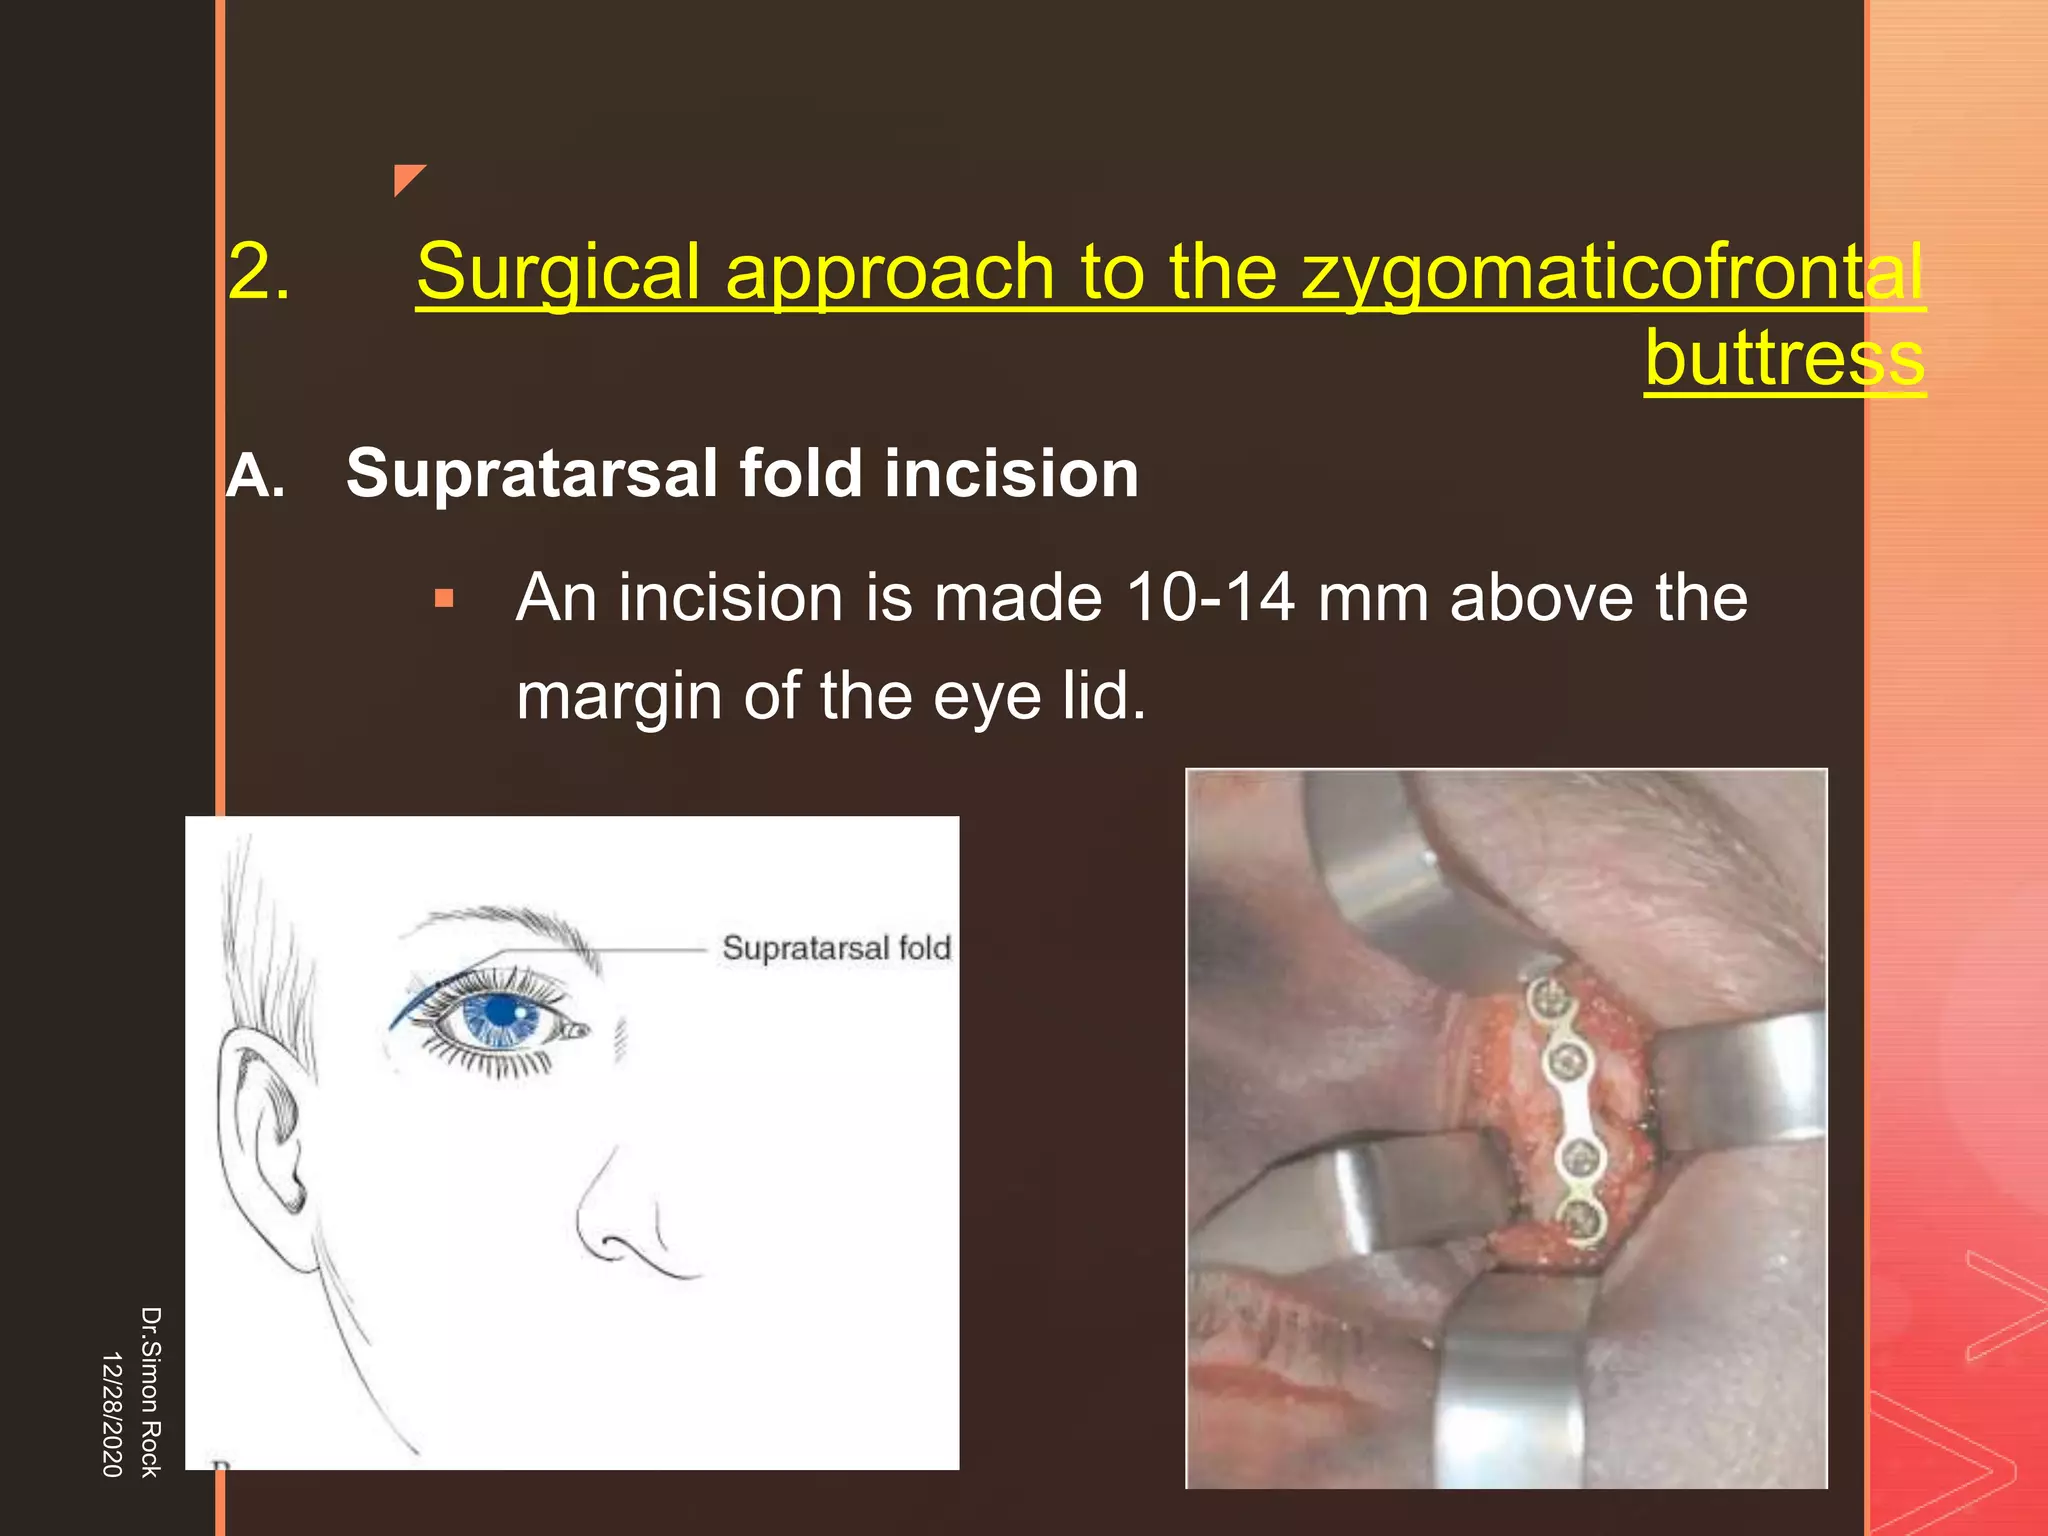

This document discusses the anatomy and fractures of the zygomatic bone. It notes that the zygoma forms the cheekbone and articulates with several other facial bones. Zygomatic fractures most commonly occur in the arch or body due to blunt trauma. Diagnosis involves checking for diplopia, ecchymosis, and other signs of orbital or facial bone involvement. Treatment may involve closed or open reduction based on the severity of displacement. Closed reduction techniques try to elevate the bone back into position without surgery, while open reduction requires surgical exposure and fixation of the fracture site.